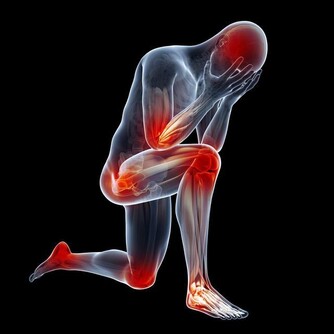

而且她的背部開始很痛、心臟開始不舒服….她才決定去找醫生!